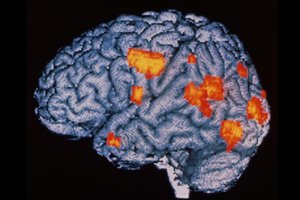

Під час перегляду світлин за допомогою магнітно-резонанснансної томографії з полем у 7 тесла вчені відстежували в учасників активність так званої блакитної плями — locus coeruleus. Також фіксували взаємодію цієї ділянки з дорсолатеральною префронтальною корою (центр когнітивного контролю).

7-Теслове МРТ дозволяє робити зображення з вищою роздільною здатністю. У випадку з аналізом роботи locus coeruleus це критично важливо, оскільки ця ділянка розміром із вівсяне зернятко.

Блакитна пляма – це два симетричні ядра у стовбурі мозку, кожне завдовжки 10–15 мм, шириною 1–2 мм і товщиною до 1 мм. Але в ній міститься від 15 000 до 60 000 нейронів.

Попри мініатюрні розміри, ця зона критично важлива, оскільки відповідальна за виробництво норадреналіну та є своєрідною “сигналізацією тривоги” для людського організму.